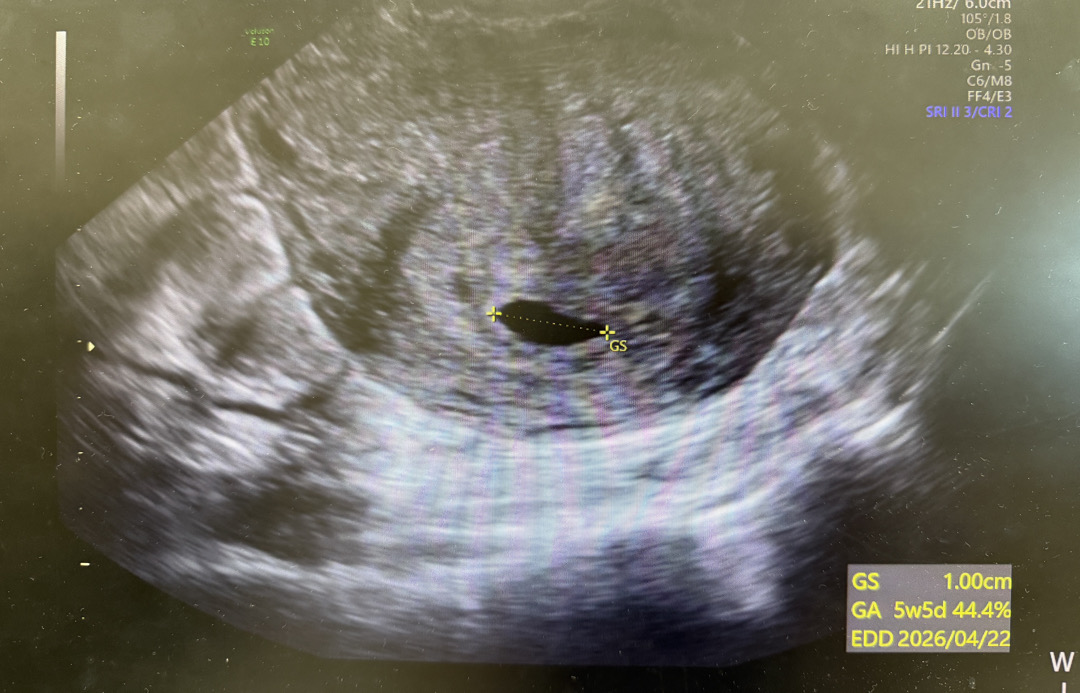

5주5일 초음파

마지막생리 시작일 7/17이고 생리주기 28-29일 입니다! 어제 달력상으로 5주5일로 초음파 보러갔어요 난황은 안보이고 아기집만 커진걸 보고와서 마음이 찝찝해서 이렇게 글 올려요ㅠㅠ 다음주에 교수님은 뵙자고 하면서 프로게스테론 질정 처방을 같이 주셨어요.. 유지 잘되겠죠..ㅠㅠ